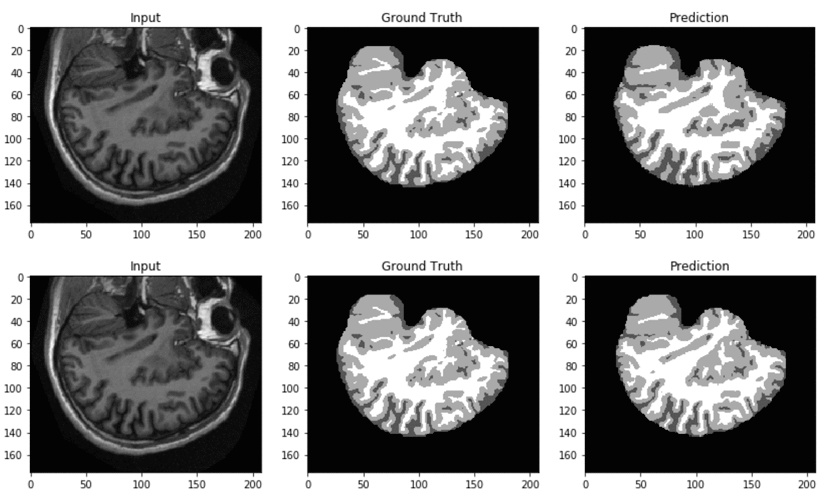

In Part 1 of this blog post, we demonstrated how to train and deploy neural networks to automatically segment brain tissue from an MRI scan in a simple, streamlined way using Amazon SageMaker. We used Apache MXNet to train a convolutional neural network (CNN) on Amazon SageMaker using the Bring Your Own Script paradigm. We […]

Annotation and segmentation of medical images is a laborious endeavor that can be automated in part via deep learning (DL) techniques. These approaches have achieved state-of-the-art results in generic segmentation tasks, the goal of which is to classify images at the pixel level. In Part 1 of this blog post, we demonstrate how to train […]